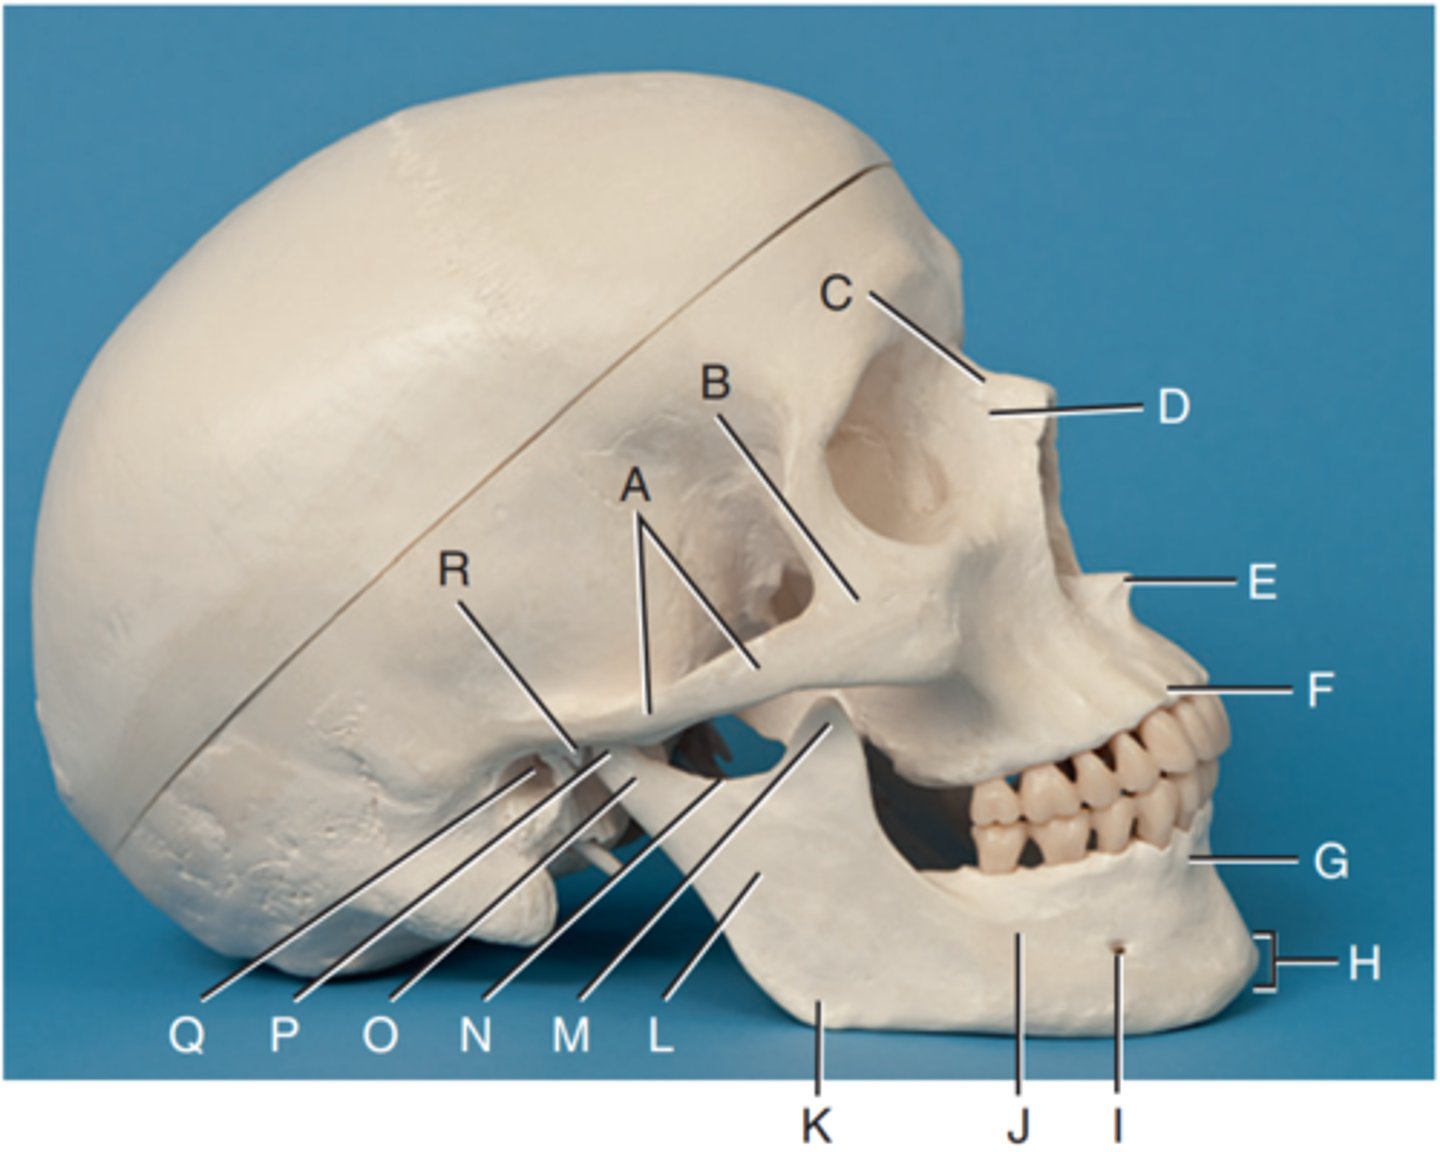

Zygomatic arch

Label A

Right zygomatic bone

Label B

Right nasal bone

Label C

Frontal process of right maxilla

Label D

Anterior nasal spine

Label E

Alveolar process of maxilla

Label F

Alveolar process of mandible

Label G

Mentum or mental protuberance

Label H

Mental foramen

Label I

Body of mandible

Label J

Angle (gonion)

Label K

Ramus of mandible

Label L

Coronoid process

Label M

Mandibular notch

Label N

Neck of mandibular condyle

Label o

Condyle or head of mandible

Label P

EAM

Label Q

TM fossa of temporal bone

Label R

Greater wings of sphenoid

Label S

Lesser wings of sphenoid with anterior clinoid processes

Label T

Ethmoid sinuses between orbits

Label U

Body of maxilla containing maxillary sunuses

Label V